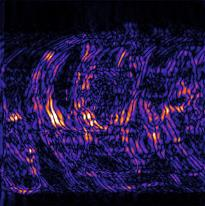

Recently, deep neural networks have greatly advanced undersampled Magnetic Resonance Image (MRI) reconstruction, wherein most studies follow the one-anatomy-one-network fashion, i.e., each expert network is trained and evaluated for a specific anatomy. Apart from inefficiency in training multiple independent models, such convention ignores the shared de-aliasing knowledge across various anatomies which can benefit each other. To explore the shared knowledge, one naive way is to combine all the data from various anatomies to train an all-round network. Unfortunately, despite the existence of the shared de-aliasing knowledge, we reveal that the exclusive knowledge across different anatomies can deteriorate specific reconstruction targets, yielding overall performance degradation. Observing this, in this study, we present a novel deep MRI reconstruction framework with both anatomy-shared and anatomy-specific parameterized learners, aiming to "seek common ground while reserving differences" across different anatomies.Particularly, the primary anatomy-shared learners are exposed to different anatomies to model flourishing shared knowledge, while the efficient anatomy-specific learners are trained with their target anatomy for exclusive knowledge. Four different implementations of anatomy-specific learners are presented and explored on the top of our framework in two MRI reconstruction networks. Comprehensive experiments on brain, knee and cardiac MRI datasets demonstrate that three of these learners are able to enhance reconstruction performance via multiple anatomy collaborative learning.